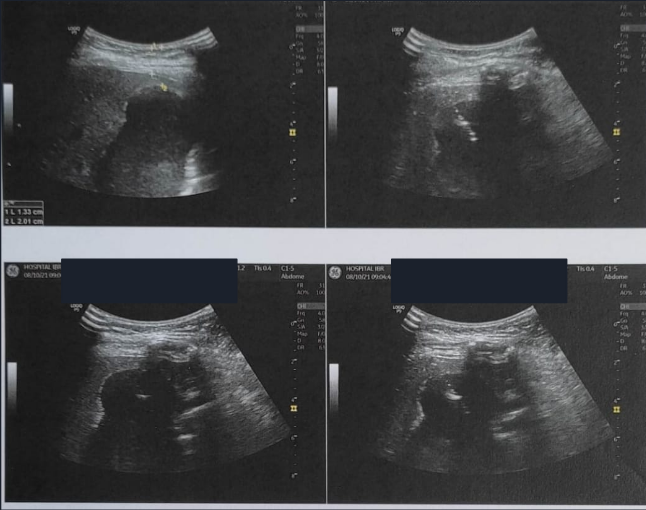

Diante desse cenário, foi indicada terapêutica minimamente invasiva combinada de Colangiopancreatografia retrógrada endoscópica (CPRE) para drenagem da via biliar e drenagem percutânea através de radiologia intervencionista para o bilioma. Ambos bem sucedidos, entretanto CPRE revelou lesão iatrogênica da via biliar (clipagem parcial do ducto colédoco) e coledocolitíase proximal à subestenose, tendo sido procedida drenagem da via biliar com prótese plástica (Fig 3). A drenagem percutânea foi guiada por USG (Fig 4) e aspirado 100ml de liquido bilioso, mantido dreno por 3 dias sem intercorrências.

Fig 4. Imagens dos achados ultrassonográficos: coleção levemente heterogênea em topografia de loja vesicular (esq.) e drenagem percutânea da coleção (dir.).